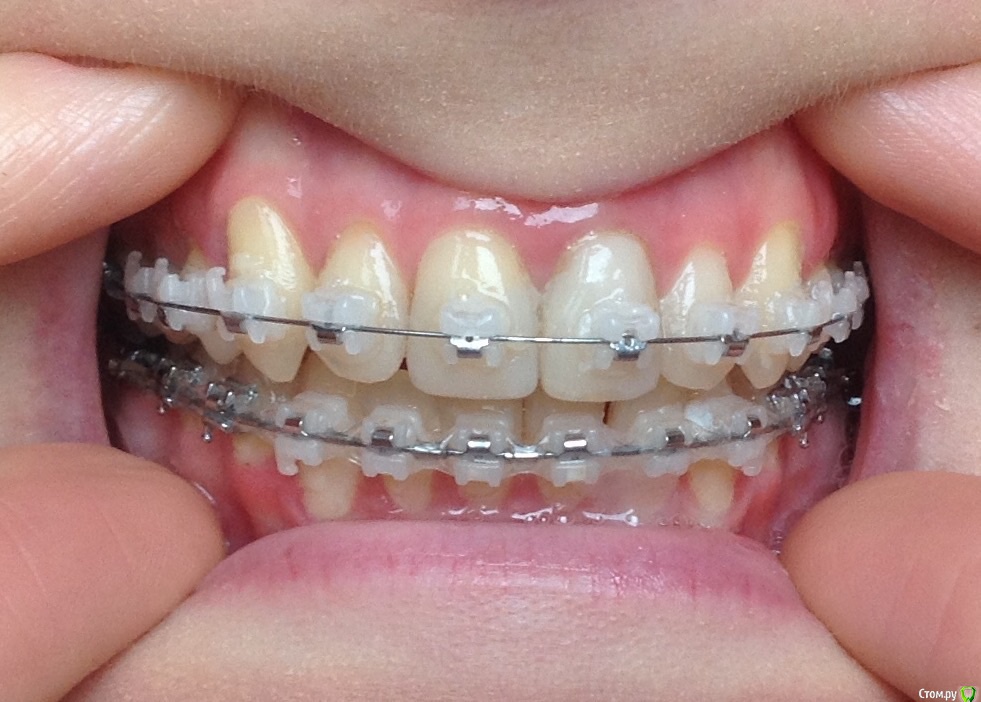

Добрый день ! Мне 29 лет. Ношу брекеты 10 мес. На данном этапе лечения сделали панорамный снимок, чтобы посмотреть ровно ли стоят корни зубов. После этого врач решил переклеить один брекет на клыке ( на снимке его видно слева ). А мне по снимку бросились в глаза , помимо этого клыка, рядом стоящий боковой резец ( он же не нравится мне как стоит и внешне) , и на нижней челюсти : 1- ый премоляр,и рядом стоящие 3 резца. Врач сказал подумать неделю и решить, хочу ли я переклеить или нет какой либо из брекетов,тк дальше они так и останутся. На её взгляд ничего переклеивать , кроме клыка, больше не нужно.

П.с. На нижн. челюсть уже поставили резинки для стягивания щелей. Я так понимаю после этого этапа уже на них брекеты не будут переклеиваться ?

Главный вопрос : Нужно ли мне переклеивать еще какие- нибудь брекеты , опускать или поднимать какой- либо из зубов, чтобы добиться большей эстетики и в дальнейшем правильного прикуса ? Или же не нужно. Заранее спасибо за внимание.